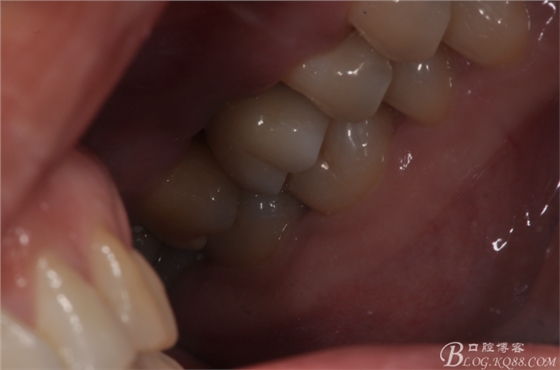

修復(fù)后口內(nèi)照片